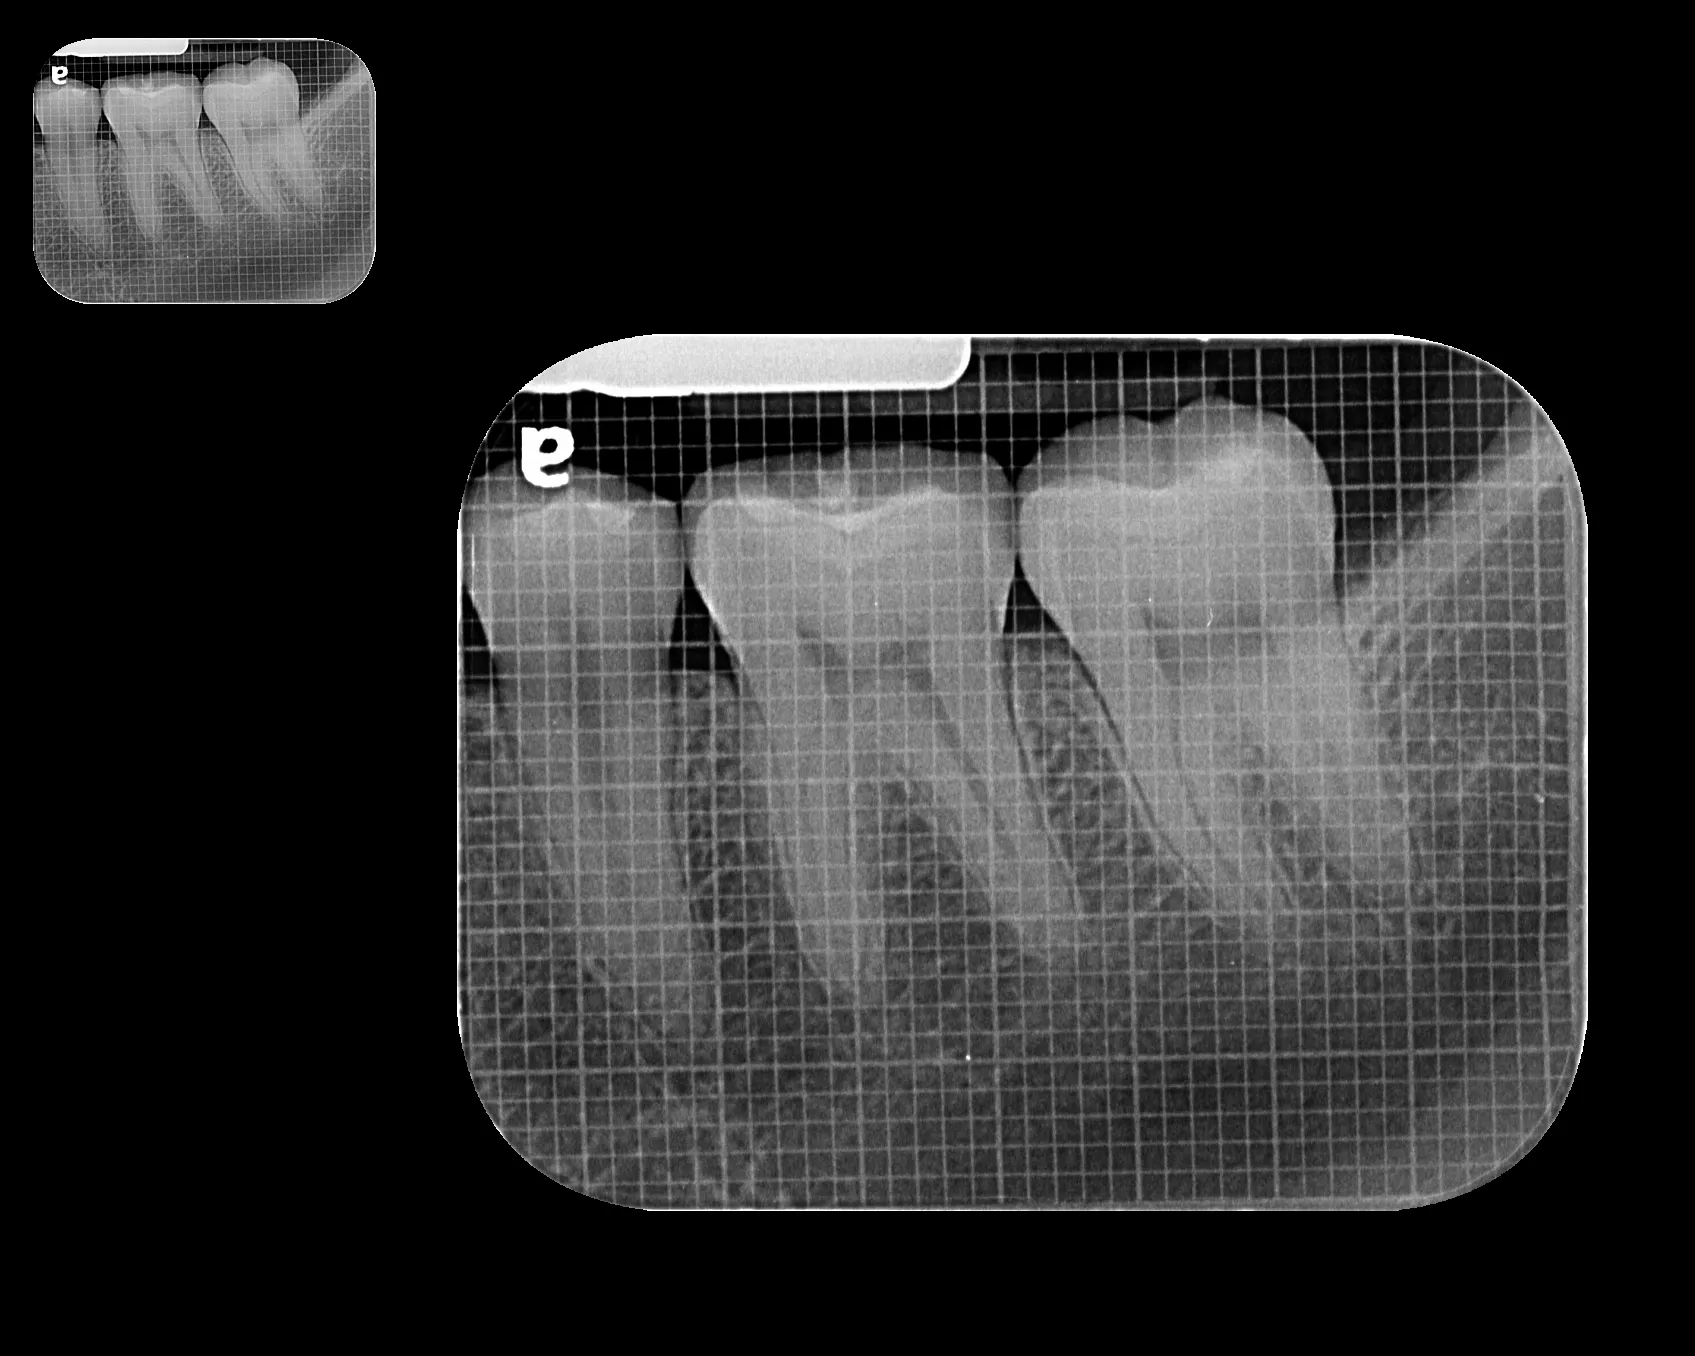

La radiografía intraoral permite observar con gran detalle los dientes y las estructuras que los rodean. Es una herramienta fundamental para detectar caries, infecciones, fracturas, alteraciones en la raíz dental o en el hueso de soporte.

En MS Radiología Dentofacial, utilizamos equipos digitales de alta precisión que reducen la exposición a radiación y garantizan imágenes nítidas para un diagnóstico confiable.